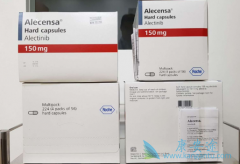

第一代 ALK靶向药 克唑替尼,不仅效果远超化疗,副作用也小很多,大大提升了患者的生活质量。但它有个无法克服的问题,就是患者一年左右几乎都会出现耐药。为了解决这个问题,科学家开发了对ALK突变基因抑制性更强,特异性更好的新一代靶向药物,比如阿 ...

去年上市的第三代EGFR-TKI 奥希替尼 ,可查的海外月治疗费用在15000美元左右(约合人民币10万元)。但在中国上市后,实际的月治疗费用为5万元,赠药计划是买4增8,相当于20万元左右可使用一年。 有奥希替尼这种先例,我们有理由相信 阿来替尼 、纳武 ...